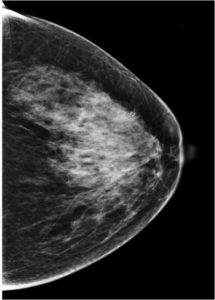

53 year old female came for routine mammographic screening...

Read More